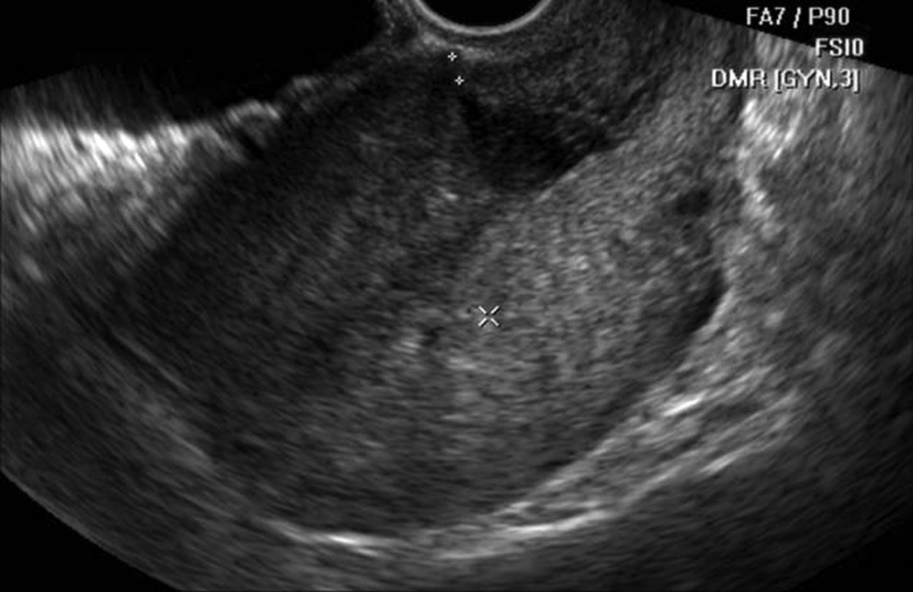

After assessing the characteristic complaints of the women studied (menstrual cycle disorders (MCD), secondary infertility, miscarriage), an ultrasound examination of the pelvic organs was performed. During TVUS of the scar area on the uterus, in addition to determining its local thinning (‘niche’), the thickness of the scar along its entire length and its homogeneity were measured. Thus, the thickness of the scar on the uterus in the main group averaged 2.85±0.3 mm.In the comparison group, the average scar thickness was 6.1 ± 0.6 mm. The thickness of the myometrium outside the scar area did not differ significantly between the study groups. Among the 72 women with uterine scar dehiscence, 51 (70.8%) showed the presence of a "niche" on ultrasound (Fig. 1), while in the remaining cases, scar heterogeneity and adhesions were observed. | Figure 1. Patient M., 27 years old, niche symptom (main group) |